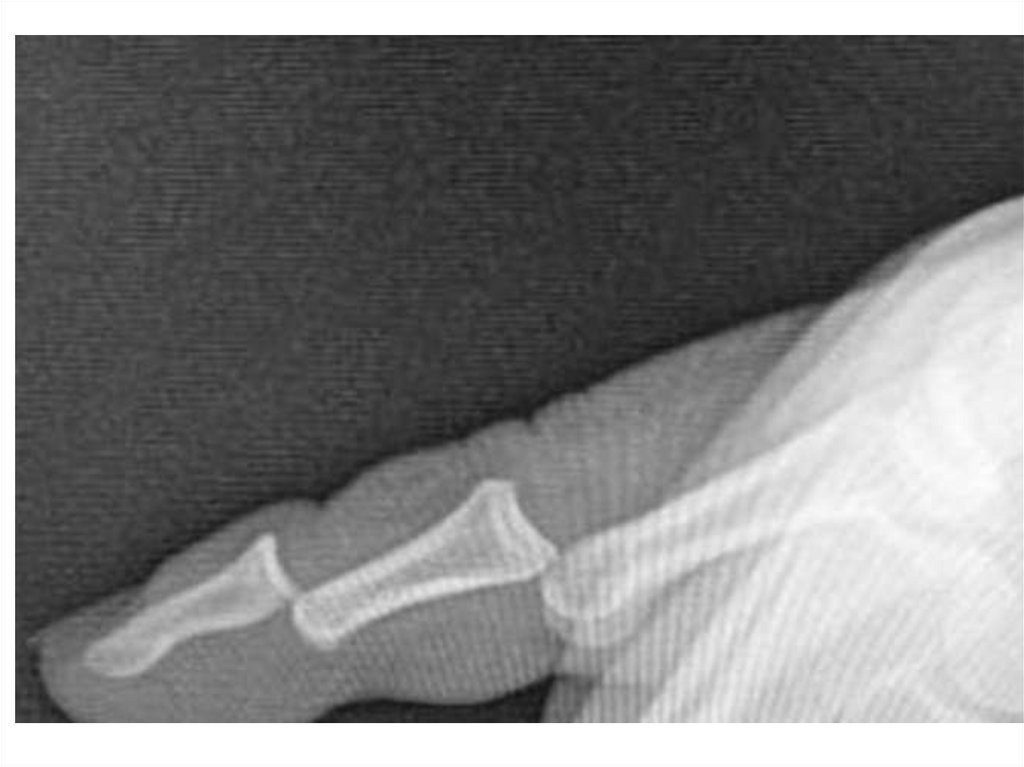

Назовите

• Вид исследования

• Область исследования

• Патологию